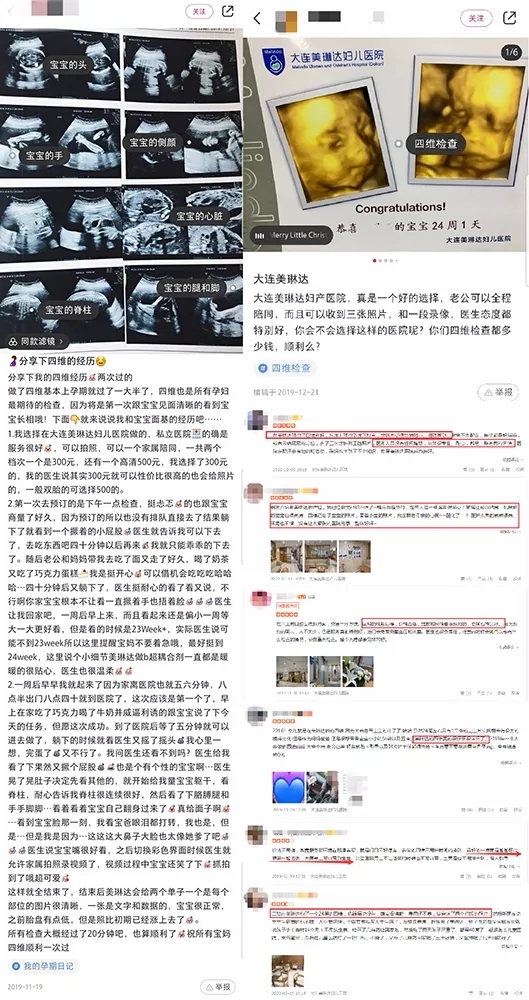

(美琳达四维彩超在大众点评、小红书上孕妈好评分享)

(美琳达四维宝宝照片)

(明星主播东玥两次四维检查胎宝照片对比)